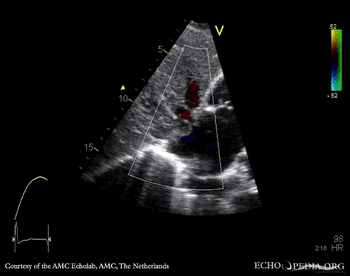

| Subcostal view | Subcostal view with color doppler |